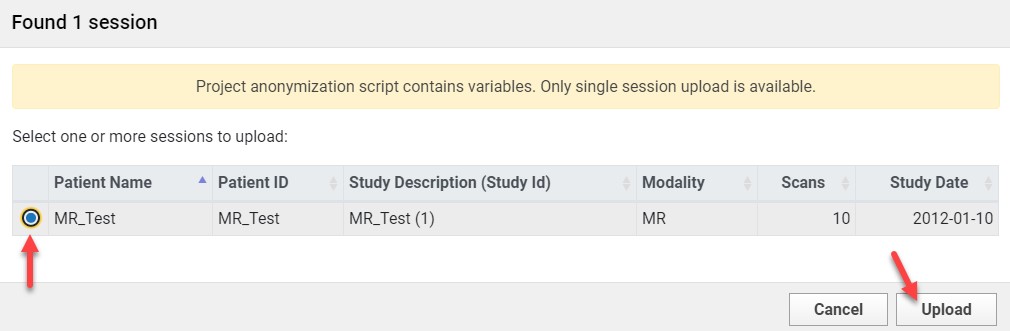

- Click Browse and select the directory containing your image files.

- If prompted with anonymization options, select the file and click Upload.

Subject and Session Setup

If Subject Already Exists

- Select the subject from the dropdown menu.

If Subject is New

- Click Create New Subject.

- Enter the Subject ID.

- Click Add New Subject.